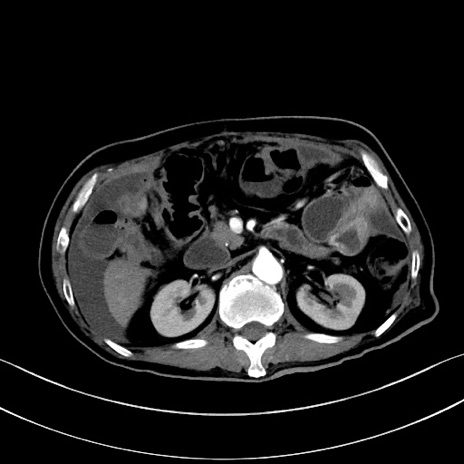

症例28(横断像)

【症例】60歳代男性

【主訴】嘔吐

【現病歴】胃癌にて胃全摘後。食思不振が悪化し、夜中に嘔吐することがある。

【既往歴】胃癌、胃全摘、脾摘、胆摘後

【データ】WBC 5900、CRP 10.56